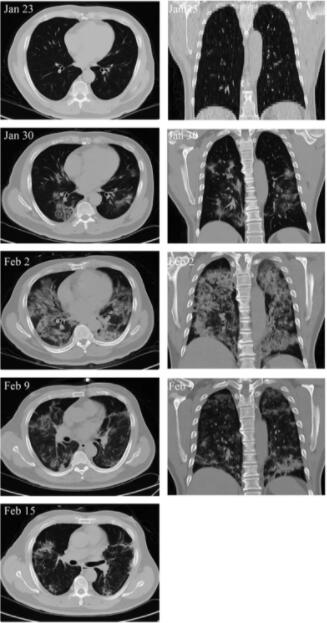

另外,MSC移植能显著加快治疗进程。移植后4天,新冠肺炎危重症患者呼吸频率降至正常范围、发烧和呼吸急促等症状消失。移植后9天,胸部CT成像显示毛玻璃样混浊和肺炎浸润已大大减少。

危重患者肺部影像学显示症状改善